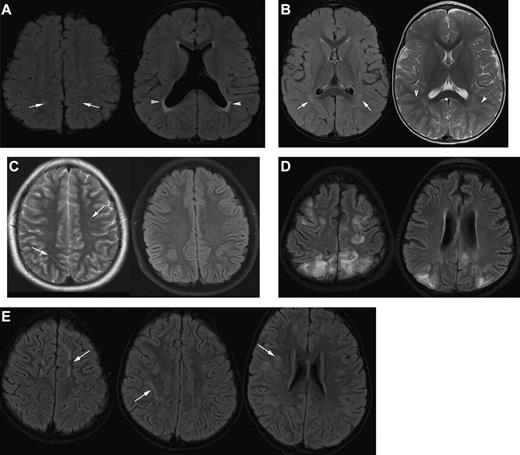

Strict guidelines for radiographic assessment of SCI require the ability to distinguish SCI from acute and chronic mimics of SCI (Figure 4). Because of the possibility of misclassification of a diagnosis of SCI when a new lesion is suspected, a dialogue between the neuroradiologist, neurologist, and hematologist should occur so both the clinical history and differential diagnoses can be carefully considered.

Differential diagnosis of silent infarction (images from patients without SCA). (A) Mimics of SCI: periventricular leukomalacia (PVL). A 20-month-old boy with cerebral palsy characterized by spastic diplegia. Axial FLAIR MR images illustrate classic findings of PVL. The image on the left is at the level of the centrum semiovale and demonstrates bilateral hyperintensities in the parietal lobe white matter. This appearance of the white matter overlaps with the presentation of SCI. The image on the right at the level of the basal ganglia illustrates dysmorphic lateral ventricles, thinning of the periventricular white matter and periventricular signal hyperintensity in a predominantly posterior distribution. Taken together, the images are consistent with the diagnosis of PVL in the setting of prematurity and cerebral palsy rather than SCI. (B) Terminal zones of myelination. A 2-year-old boy with a normal MRI of the brain. The Axial FLAIR MR image (left) shows ill-defined hyperintensity bilaterally in the deep white matter adjacent to the atria of the lateral ventricles (arrows). The T2-weighted image on the right illustrates that there are well-defined linear perivascular spaces (arrowheads) traversing the area of vague hyperintensity. This combination of findings is classic for the terminal zones of myelination, the last areas of the deep white matter to myelinate and displace free water. The terminal zones of myelination remain prominent through the second year of life and become progressively less conspicuous over time. They may be visible into the middle of the first decade of life. (C) Virchow-Robin spaces. A 12-year-old boy withT2-weighted (left) and Axial FLAIR (right) MR images with a normal MRI. The T2-weighted images reveal multiple punctuate white matter hyperintensities that suppresses on FLAIR indicating that the hyperintensities are indistinguishable from cerebrospinal fluid. The fluid attenuation feature of the FLAIR image helps to differentiate perivascular (Virchow-Robin) spaces from SCI. The arrows illustrate another feature of perivascular spaces which is that they appear linear when running within the slice. (D) Posterior reversible encephalopathy syndrome (PRES). A 14-year-old girl with altered mental status and seizures. Axial FLAIR MR images demonstrate hyperintensities bilaterally in the subcortical white matter and overlying cortex with predominant subcortical involvement. The distribution of the signal abnormalities is predominantly posterior and peripheral, a typical distribution for PRES. In contradistinction, SCIs favor the deep white matter of the frontal lobes. Nevertheless, clinical context is the key to differentiating PRES from SCIs. This is especially challenging in patients with SCD because they are prone to development of PRES and SCI. (E) Acute disseminated encephalomyelitis (ADEM). A 5-year-old boy with fever and headache. Axial FLAIR MR images demonstrate patchy, bilateral hyperintensities in the white matter of the centrum semiovale and corona radiata (arrows). Although the image on the left could be confused for SCI in the frontal border zone distribution, the middle and right image show subcortical and patchy hyperintensities that would be atypical in location, size, and lesion definition for SCI. The clinical information is the key to distinguishing lesions of ADEM from SCI.